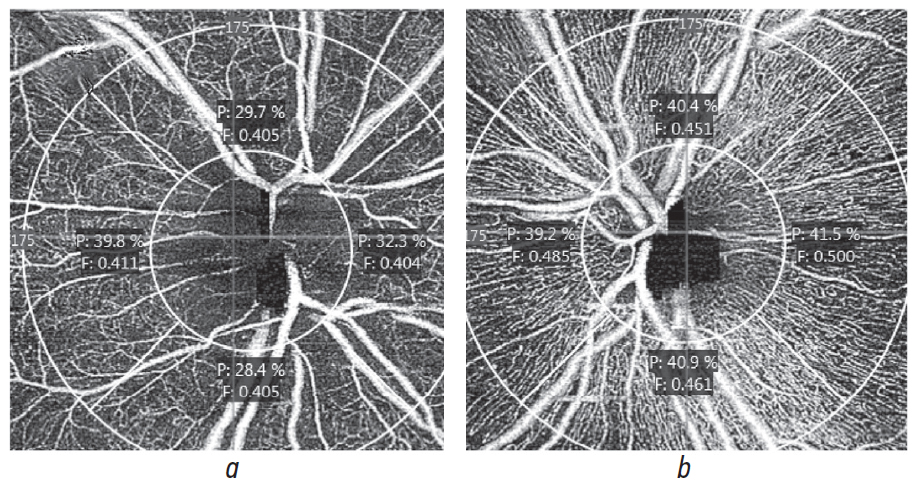

At angio-OCT performed at the same time point (6 months), a significant decrease in retinal capillaries density and perfusion decrease, both in parapapillary (Fig. 5), and macular areas (Fig. 6). Secondary optic nerve atrophy is a typical outcome of AION. Not typical are enlargement of optic disc excavation, progressing atherosclerotic changes, and diabetic retinopathy regression only in one eye. The explanation for it possibly is an ischemia of the right eye caused by prior vascular accident.

Fig. 5. AngioOCT of the optic nerve head, 6 months after the first examination. Optic nerve head perfusion indices of the right (а) and left (b) eye. Mean values of perfusion density are 32.9 and 40.5 %, respectively

Рис. 5. Данные оптической когерентной томографии в режиме ангиографии диска зрительного нерва пациента через 6 мес. после первого осмотра. Показатели перфузии диска зрительного нерва правого (а) и левого (b) глаз. Средние значения плотности перфузии составили 32,9 и 40,5 % соответственно

Fig. 6. AngioOCT of the patient, 6 months after the first examination. Vascular density indices (mm/mm2) of the superficial vascular plexus in the macular area of the right (а) and the left (b) eye, and vascular density indices of the parapapillary plexus of the right (c) and the left (d) eye. A decrease in vascular density in all measurement areas on the involved side is noted

Рис. 6. Данные оптической когерентной томографии в ангиорежиме пациента через 6 мес. после первого осмотра. Показатели сосудистой плотности (мм/мм2) поверхностного сосудистого сплетения в макулярной зоне правого (а) и левого (b) глаз и показатели сосудистой плотности парапапиллярного сплетения правого (с) и левого (d) глаз. Отмечается снижение сосудистой плотности во всех участках измерения на стороне поражения